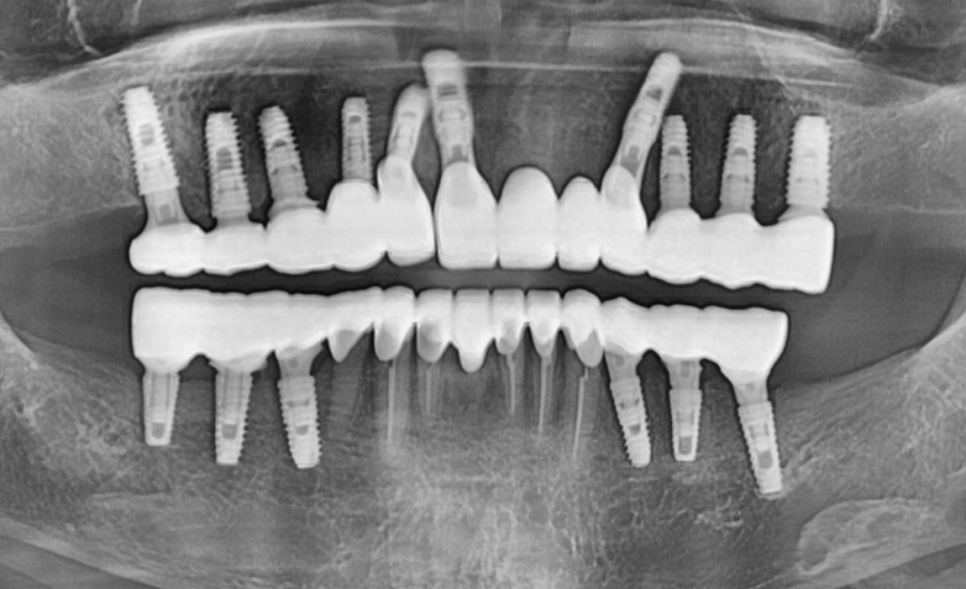

230211

입안을 보니

앞니뿐 아니라 어금니까지 평평하게 닳아 있었고,

오른쪽 아래 임플란트 보철이

유난히 낮게 제작되어 있었습니다.

240510

결과적으로,

아래 앞니 7개는 크라운으로 살리고,

총 12대의 임플란트를 더 식립하여

임플란트 보철로 수직 고경을 다시 세우는 방식으로

전체 교합을 재구성했습니다.

230211 (전) 240510 (후)